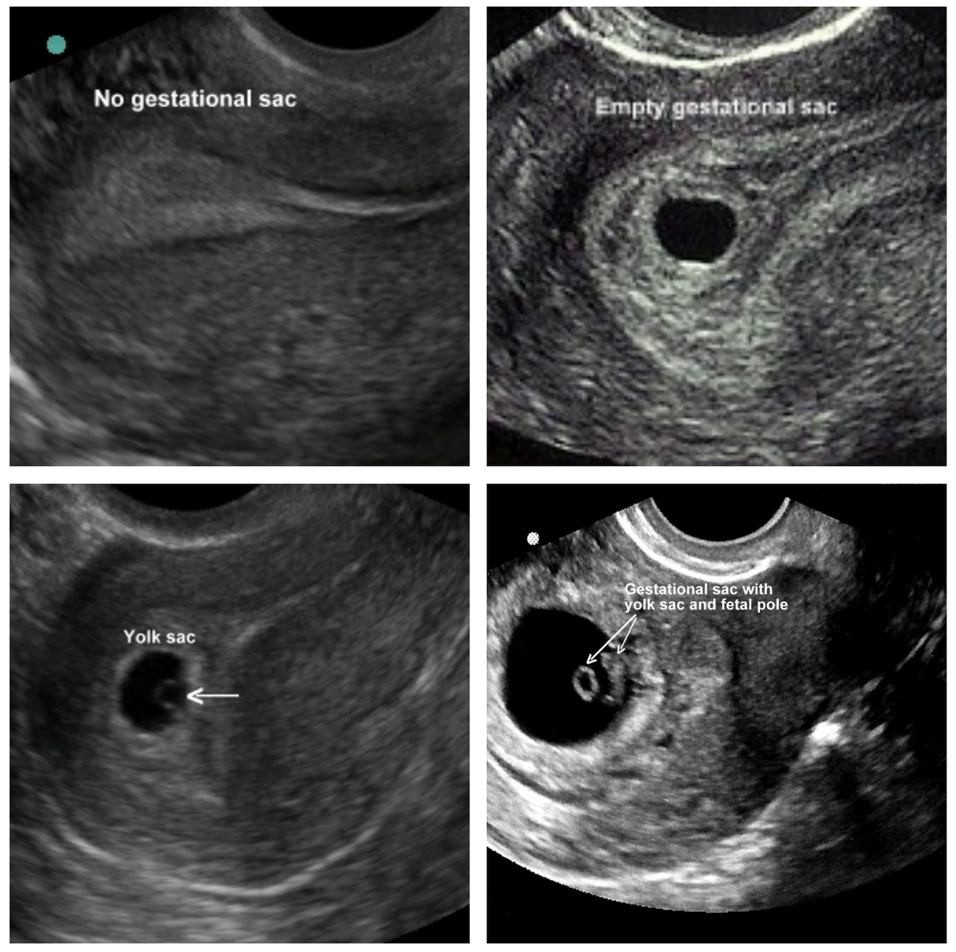

ULTRASONIDO TRANSVAGINAL PARA LA DETECCIÓN PREOPERATORIA DE

Source: sochog.cl